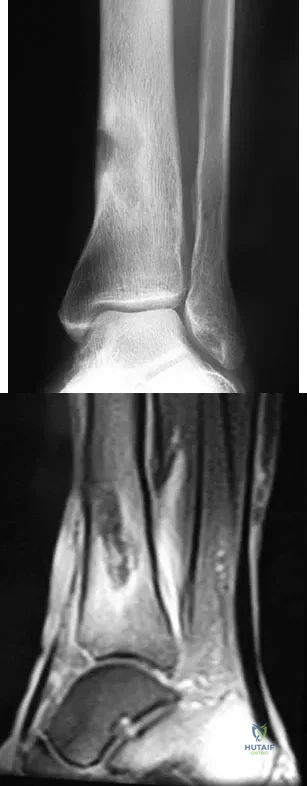

Question 31

A 68-year-old woman who sustained a closed distal tibia fracture 2 years ago was initially treated with an external fixator across the ankle for 12 weeks, followed by intramedullary nailing of the fibula and lag screw fixation of the tibia. She continued to report persistent pain so she was treated with a brace and a bone stimulator. She now reports pain in her ankle. Examination reveals ankle range of motion of 8 degrees of dorsiflexion to 25 degrees of plantar flexion. She is neurovascularly intact. Current radiographs are shown in Figures 9a through 9c. What is the next most appropriate step in management?